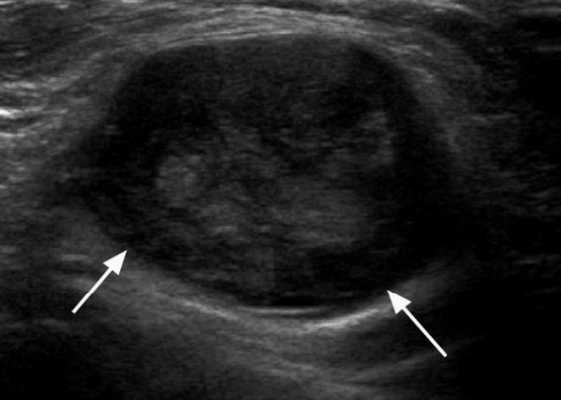

Ультрасонографические данные при шейной лимфаденопитии

- Гипоэхогенная кора по сравнению с соседней мышцей ± кортикальная гипертрофия

- Обычно овальной формы, за исключением подчелюстных узлов, которые обычно округлые

- Увеличенный лимфоузел, сохранилась хиларская архитектура. рубчик; интранодальный, линейный, эхогенный и непрерывный с границей с мягкими тканями вокруг лимфатического узла. Хиларная эхогенность обусловлена наличием множества звукоотражающих поверхностей от афферентных и эфферентных лимфатических узлов, артерий и вен, расположенных в пределах шеи и грудины.

- Граница может быть плохо определена из-за периаденита, который размывает края лимфатических узлов

- Отсутствие интранодального некроза или узлового матирования

- Соседние мягкие ткани явно не воспалены. Нет признаков сопутствующего целлюлита или абсцесса